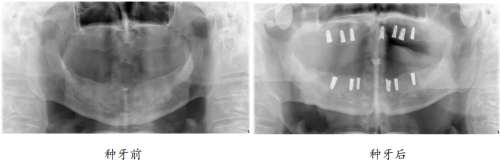

“口福行动”让80岁高龄老人缺牙重生

82岁的孙爷爷,10年前就已全口无牙,一直戴着活动假牙勉强吃饭。

近3年,活动假牙松动厉害,一吃东西就脱落,孙爷爷只能喝打成糊状的蔬菜和肉,“我看到这些,一点胃口都没有,肚子还空着,嘴里又吃不下,不知道是饿还是饱。总之吃饭好似‘上刑场’一样。”牙齿的缺失,让孙爷爷无比怀念老伴做的红烧肉,渴望重新拥有一口健全、有强劲咀嚼力的好牙,回到可以开怀大笑的日子。

偶然间,在社区举办的“修复失牙·口福行动”公益活动,实现了孙爷爷的种牙梦。

如今种牙1年后,孙叔叔的生活质量得到改善,一日三餐饮食结构丰富,红烧肉、苹果、坚果样样都能轻松消化,“多亏在‘修复失牙·口福行动’公益活动上遇见綦健院长,我现在精气神十足,邻居都说我年轻了10岁。”重获新牙的孙爷爷高兴道。